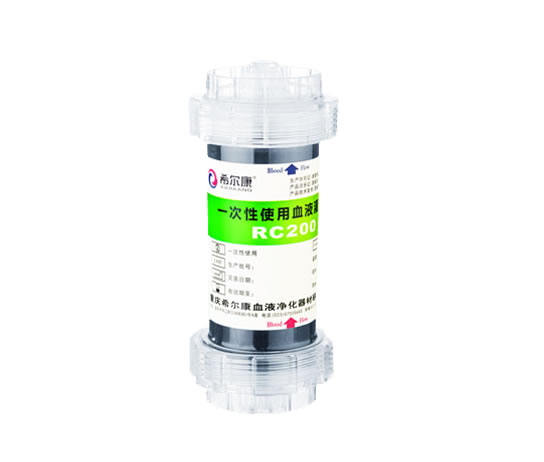

树脂炭血液灌流器-RC200

RC系列

树脂炭血液灌流器-RC200

快清®树脂炭血液灌流器